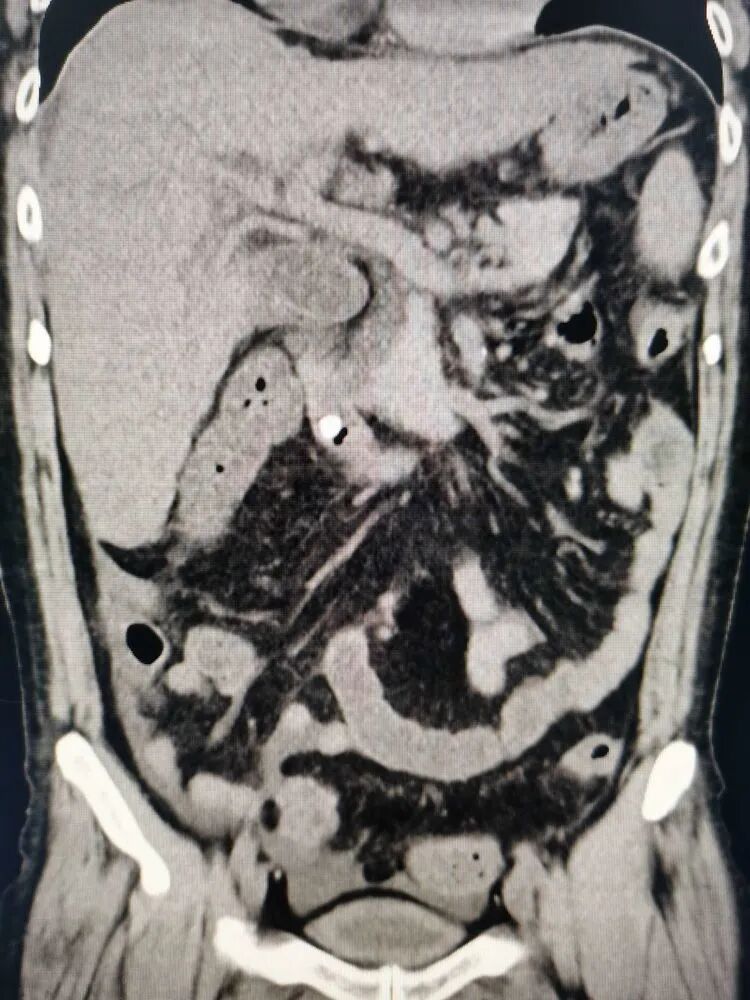

入院后完善相关检查,明确诊断后,边补液抗休克治疗,边紧急手术准备,果断行急诊ERCP手术,术中见胆总管末端结石嵌顿,胆道完全梗阻!如下图所示。

针状刀预切开大乳头后,结石取出,见大量黄白色脓性胆汁喷涌而出!

顺利取出结石,胆道内冲洗出大量脓性胆汁!腹疼立马消失,术后恢复顺利,目前已正常进食!